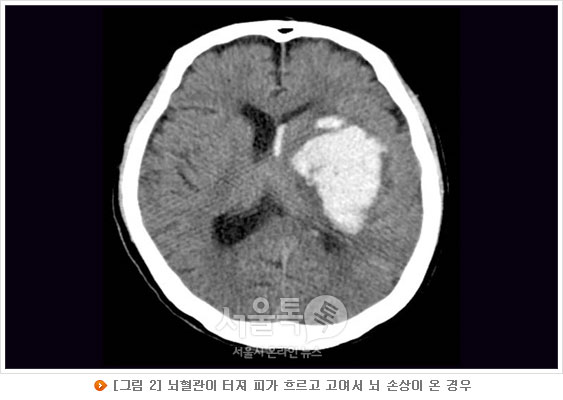

뇌출혈(출혈성 뇌졸중)의 원인에는 고혈압성 뇌출혈, 뇌동맥류 파열로 인한 뇌지주막하 출혈, 뇌혈관 기형에 의한 뇌출혈 등이 대표적이며 이외에도 뇌종양, 모야모야병, 혈관염, 혈액질환 등이 뇌출혈의 원인이 된다.